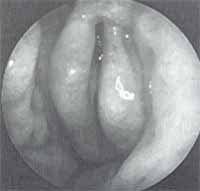

Figura 9. Endoscopia nasal practicada a paciente que se sometió a septoplastia nueve meses antes, que muestra una importante desviación septal obstructiva con cresta, espolón y sinequia izquierda. En la porción superior nótese el cornete medio aprisionado por el trastorno obstructivo.

Figura 13. Endoscopia nasal del caso anterior en el que se aprecia un proceso unciforme y un agger nasi prominentes. Ambos hallazgos son factores predisponentes de sinusitis crónica y explicaban el proceso inflamatorio sinusal del lado contrario a la desviación.